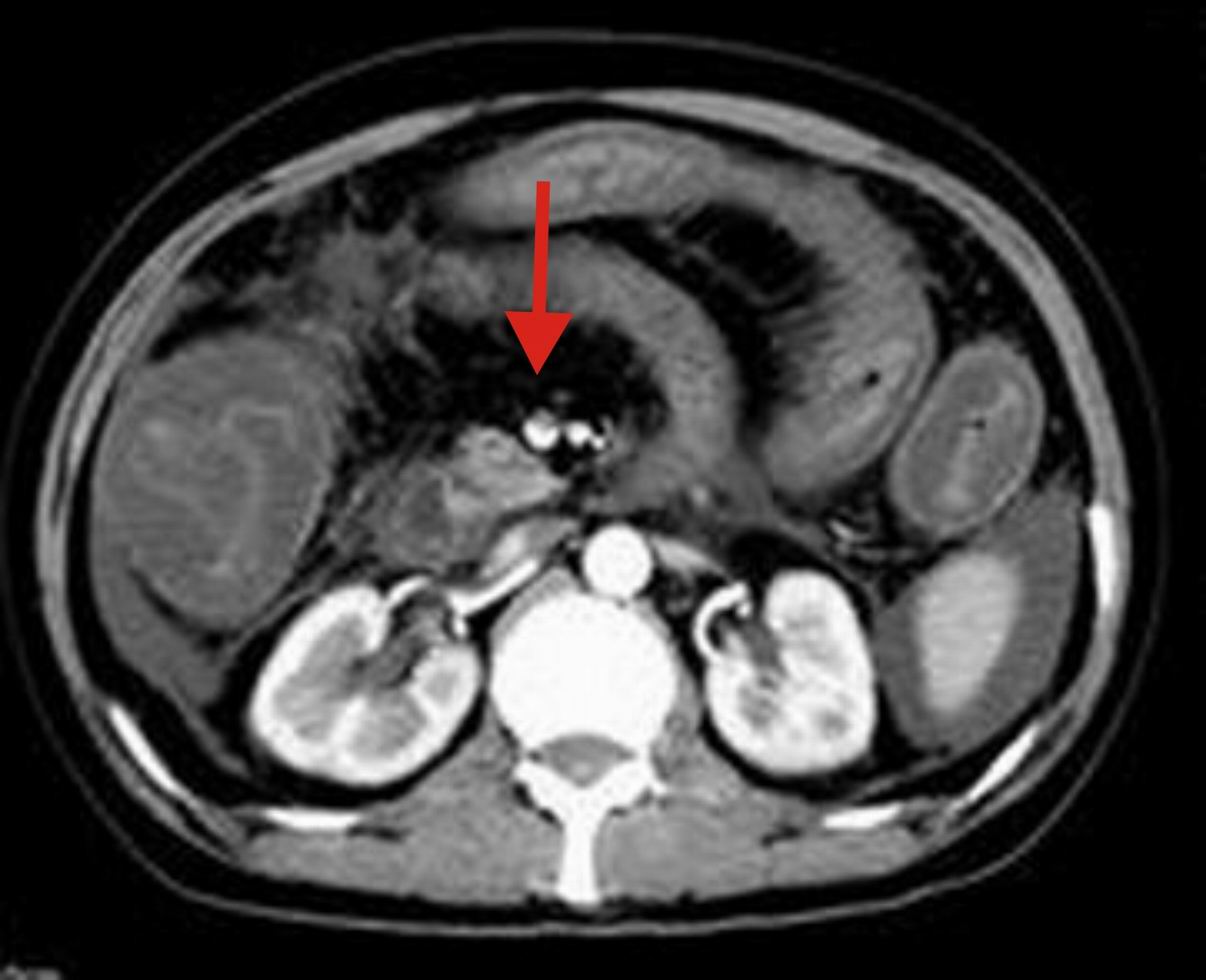

这个病例有脱发的病史,后转到风湿科,确诊为sle,经过一段时间的激素治疗,病情好转,以下是今日复查的ct

系统性红斑狼疮(sle)是一种累及多系统多器官,临床表现复杂,病程迁延反复的自身免疫性疾病。 sle的临床表现无固定模式,病程迁延,反复发作,间有长短不等的缓解期,起病可为暴发性、急性或隐匿性。

其中,消化系统症状:可出现恶心、呕吐、腹痛、腹膜炎、肠系膜血管炎、肝酶增高等。

糖皮质激素治疗,能抑制炎症细胞聚集,具有抗增殖和免疫抑制作用,是最强力的抗炎剂,是治疗sle的最主要药物,是sle的基本疗法。